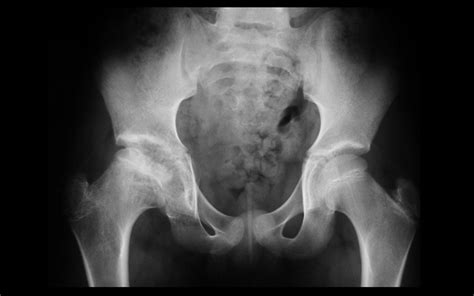

Avascular necrosis (AVN), right femoral head epiphysis ...

Avascular necrosis (AVN), right femoral head epiphysis ... from farm4.staticflickr.com